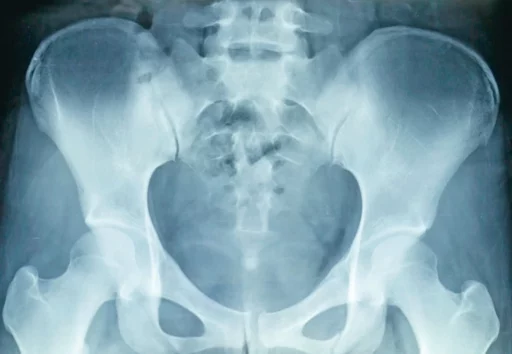

L’incidence radiographique de « De Sèze »Pour le diagnostic de l'inégalité de longueur des membres inférieurs

Des douleurs dans le genou, au bas du dos, dans les pieds lors des appuis ou encore une sensation d’inconfort du bassin… Autant de symptômes qui peuvent accompagner une inégalité de longueur des membres inférieurs. La pratique d’une radiographie appelée « incidence de De Sèze » permet alors un diagnostic de certitude.